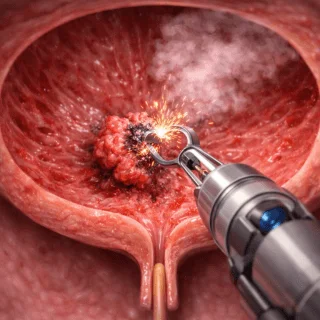

RTUV

Procedimiento endoscópico que permite diagnosticar y tratar tumores en la vejiga; además, facilita una evaluación directa de la lesión.